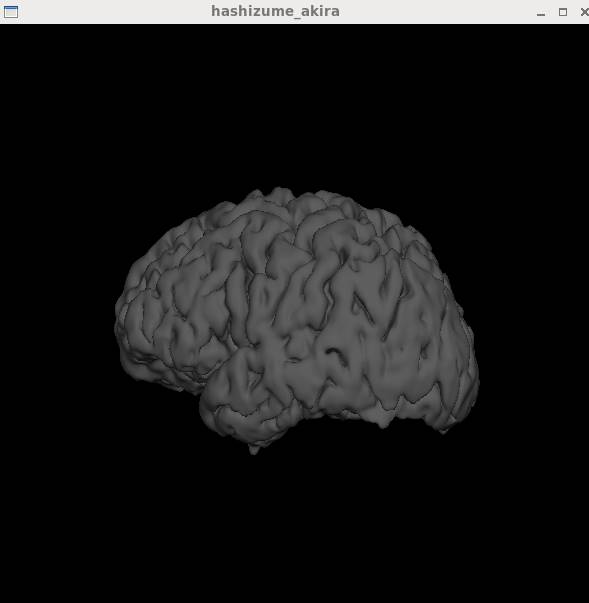

freeviewで読んでみました。

エラーは出ますが、とりあえず読めます。

一旦tksurferで

tksurfer 被検者名 lh pial

とかで起動後に表面を選択するという方法であればGIfTIファイルを直接読み込めます。

File→Load Surface…を選択し、そこでgiiファイルかmris_convertで変換したファイルを読みます。

GIfTIファイルが読みこめました。